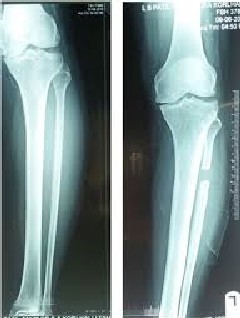

Вкратце, боковой разрез от 3 до 5 см делается в проксимальной трети малоберцовой кости. Затем фасцию рассекают, мышцы отодвигаются, малоберцовую кость обнажают. Проводится резекция малоберцовой кости длиной 2 см на 6-10 см ниже головки малоберцовой кости с помощью осциллирующей пилы. После резекции концы малоберцовой кости замазывают костным воском. Мышцы, фасции и кожа ушиваются послойно.